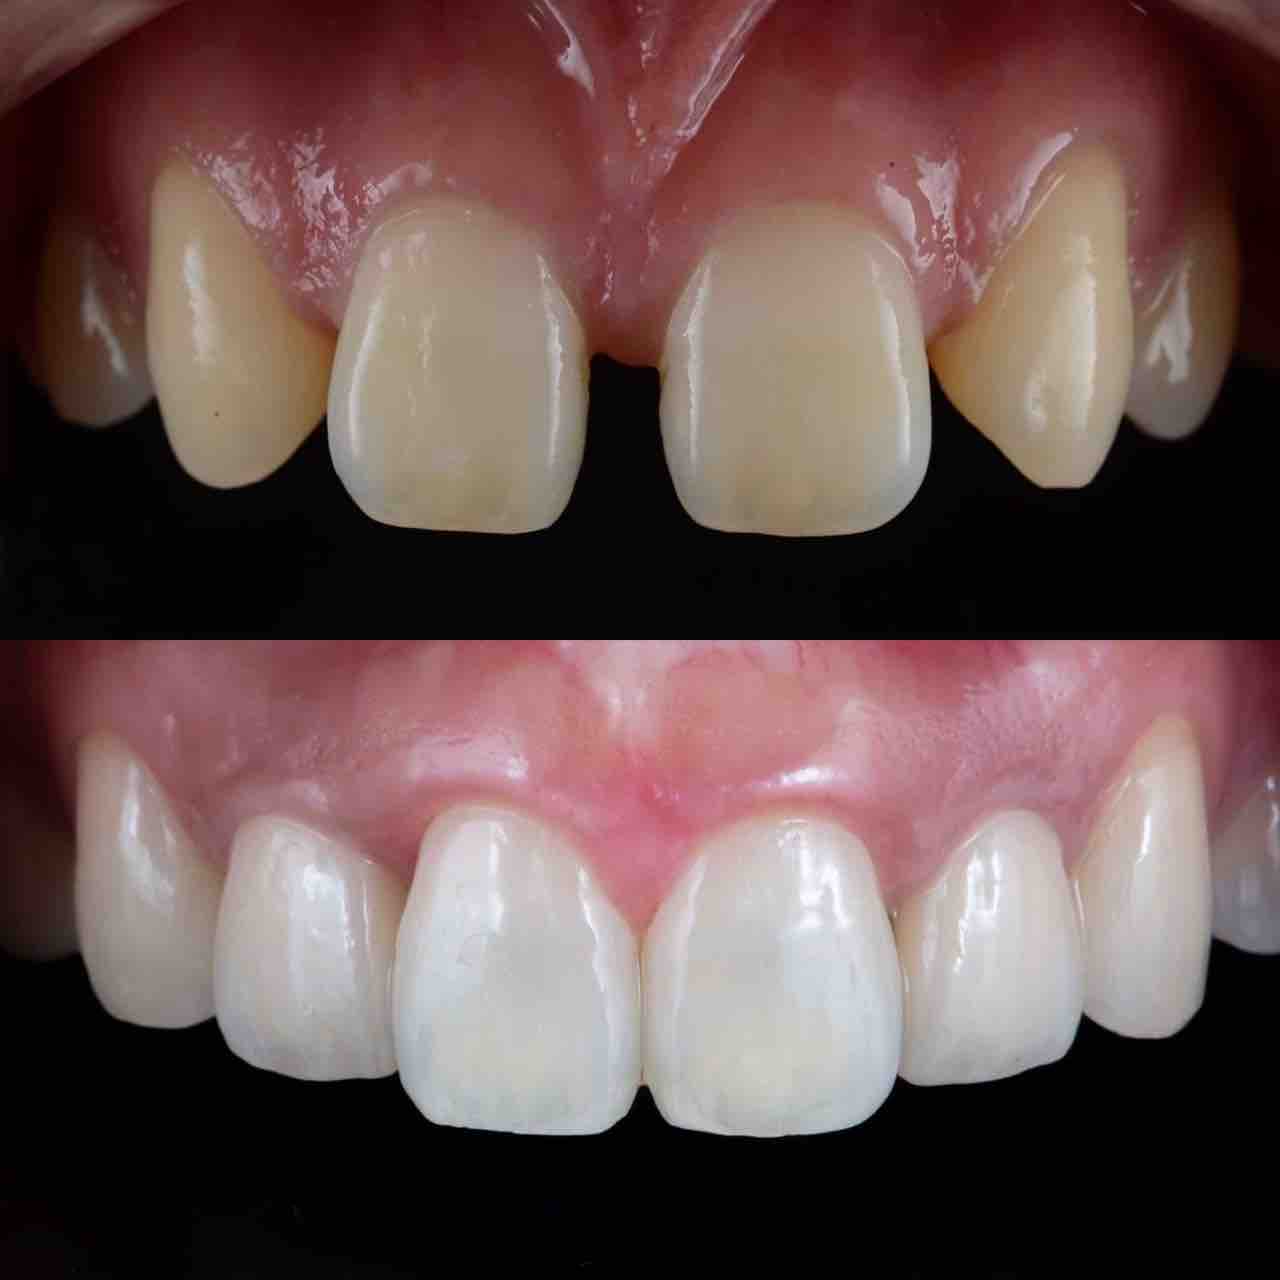

¥¤¥ó¥¹¥¿¥°¥é¥à¤ËºÜ¤»¤Æ¤¤¤ëÅö±¡¤Î¾ÉÎã¤Ç¤¹

ðÌî»õ²Ê¾ÉÎ㢠ÀèÅ··ç»¶ºÀµ¥¤¥ó¥×¥é¥ó¥È

ðÌî»õ²Ê¾ÉÎã¡¶ºÀµ¥¤¥ó¥×¥é¥ó¥È¥»¥é¥ß¥Ã¥¯